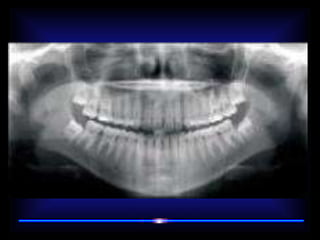

RADIOGRAFIAS DX ODONTOLOGICO •ANTERO POSTERIOR • A.P DE TOWNE • A.P. DE WATERS • PROYECCIONES LATERALES • PROYECCION A. DE CADWELL • PANORAMICA • PERIAPICAL • R.BITE WING